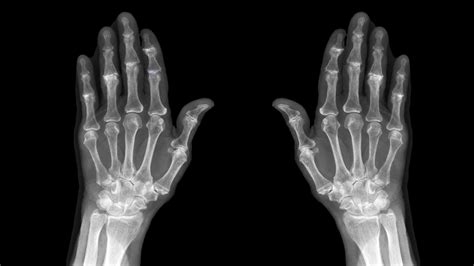

A Hand X Ray is a type of radiography that uses electromagnetic radiation to produce images of the internal structures of the hand. This process involves passing X-rays through the hand and capturing the resulting image on a detector. The varying densities of different tissues—such as bone, muscle, and fat—absorb the X-rays differently, creating a contrast that allows for detailed visualization.

Interpreting Hand X Ray results requires a trained eye. Radiologists and orthopedic specialists are typically responsible for analyzing the images. Key areas of focus include:

• Bone Density: Variations in bone density can indicate fractures, tumors, or other abnormalities.

• Joint Spaces: Narrowing of joint spaces can be a sign of arthritis.

• Soft Tissue: While X-rays primarily focus on bones, they can also provide some information about soft tissues, such as swelling or the presence of foreign bodies.